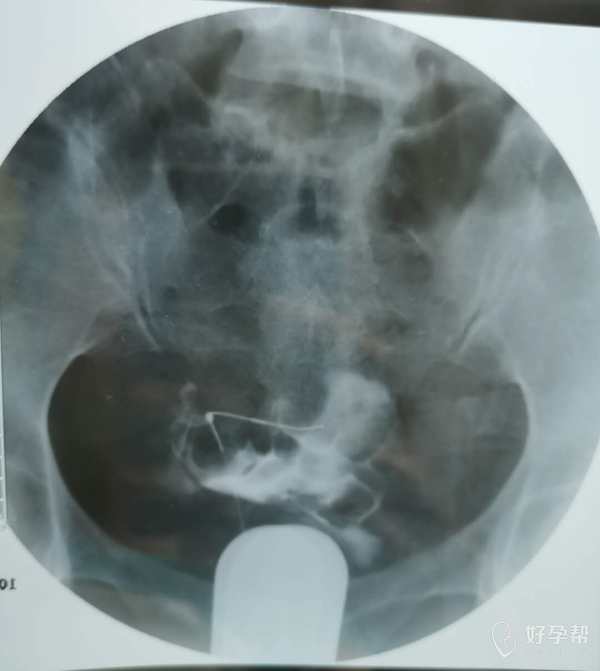

我这个是做了输卵管介入手术,请问输卵管是通了

你的片子提示双侧输卵管不通,未孕4年,合并腺肌症和腺肌瘤,建议你直接试管婴儿助孕。试管前不需要宫腹腔镜检查。